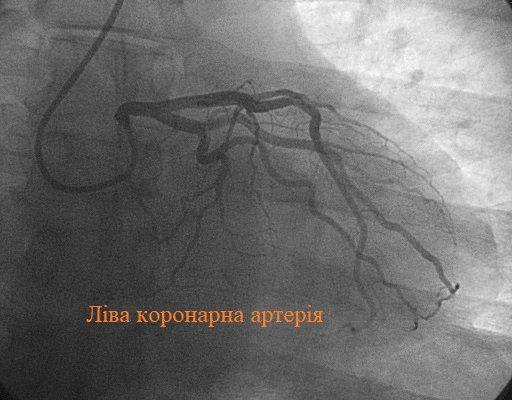

Що таке коронарографія? Коронарографія — це не просто складне медичне слово, яке важко вимовити. Це — ваш путівник у світі серцевих проблем.